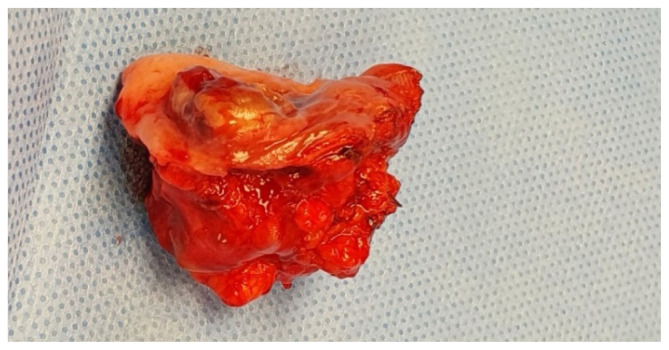

Case report: In this paper, we detail a case of PAC that developed in the buccal mucosa, which is a less common anatomical location. We discuss the patient's clinical presentation, imaging findings, histological examination results, as well as the surgical treatment and follow-up outcomes. We also examine relevant literature related to the topic to provide a comprehensive understanding of this rare case.